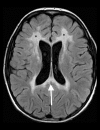

Toxic leukoencephalopathy results from damage to the white matter caused by various toxins. It manifests itself as white matter signal abnormalities with or without the presence of restricted diffusion. These changes are often reversible if the insulting agent is removed early, with the exception of posthypoxic leukoencephalopathy that can manifest itself 1-2 weeks after the initial insult. However, many other potential causes of white matter signal abnormalities can mimic the changes of toxic leukoencephalopathy. Thus, familiarity with the causes, clinical presentation and particularly imaging findings of toxic leukoencephalopathy is critical for early treatment and improved prognosis. The purpose of this pictorial essay is to familiarize the reader with the various causes of toxic leukoencephalopathy along with its differential diagnoses and mimics.